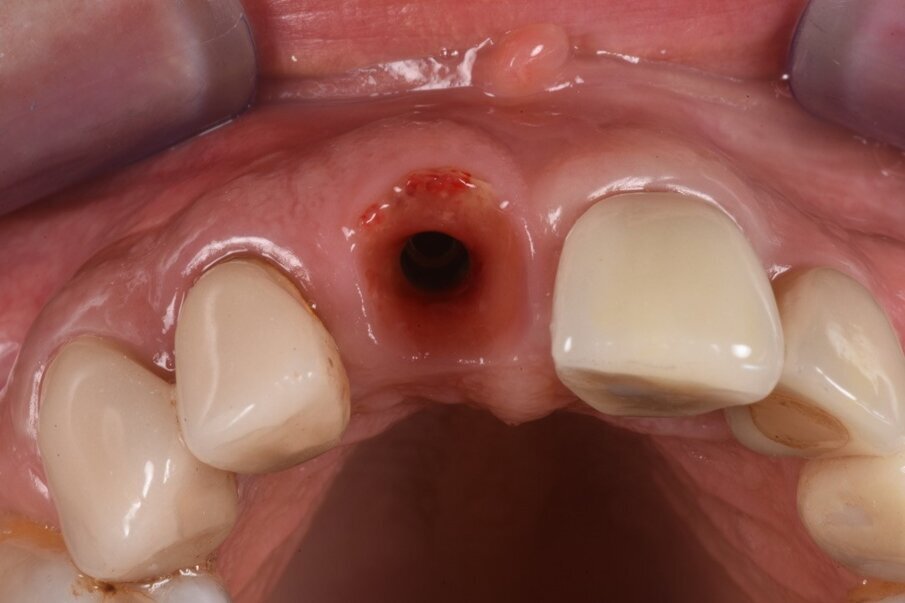

A questo punto veniva avvitato sull’impianto un moncone provvisorio, completato l’innesto di materiale biocompatibile con osso equino collagenato (OX granules, Bioteck) nel gap esistente tra la fixture e la lamina, poi veniva connessa al moncone provvisorio la corona provvisoria in resina (Fig. 13). La rx di controllo post intervento evidenzia la buona riuscita della procedura e la corretta connessione tra moncone e fixture (Fig. 14). Sei mesi più tardi alla rivalutazione e rimozione della corona provvisoria (Fig. 15) si può ben notare come questa procedura abbia permesso di mantenere integri i tessuti peri-implantari, di aver favorito la creazione di un tunnel mucoso spesso e maturo. I tessuti con e senza la corona provvisoria mostrano un aspetto naturale e le caratteristiche di una gengiva in salute (Figg. 16a, 16b).